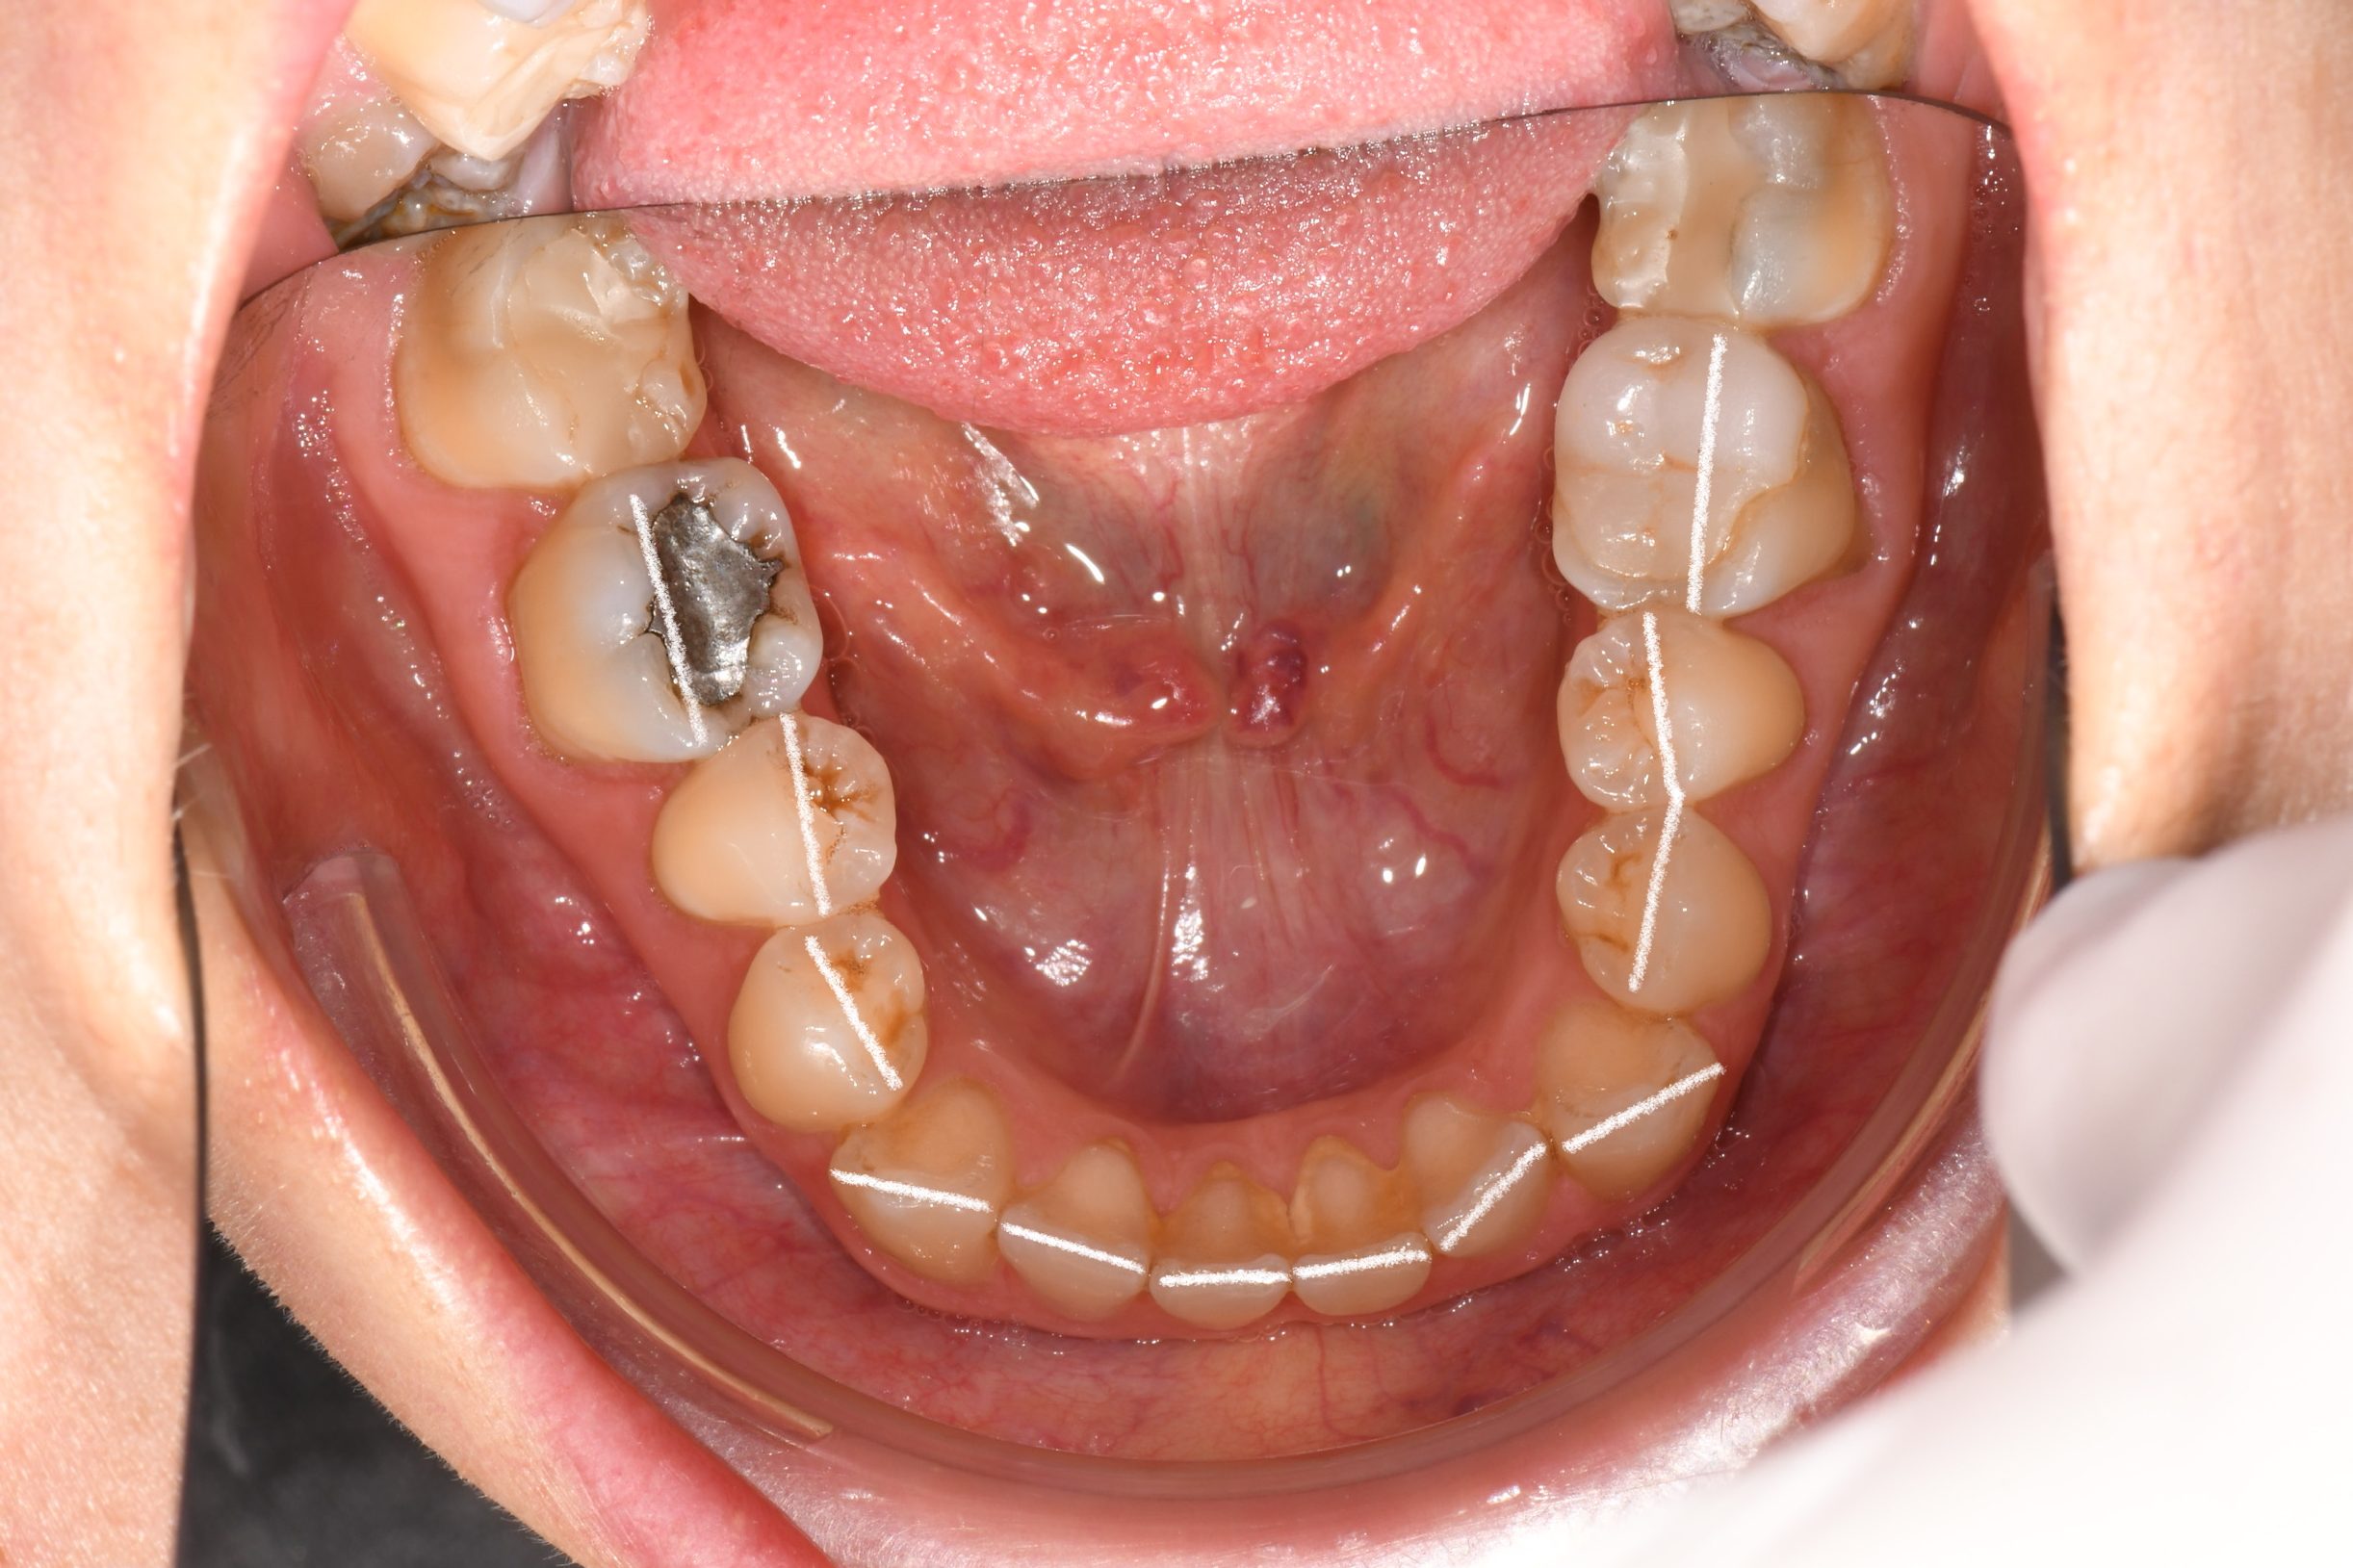

Az elmúlt évekből rengeteg szakmai referenciát tudnánk bemutatni, amelyek különböző fogszabályozási problémákat oldottak meg. Válogatva a több száz esetből, ezen az oldalon olyan képeket, információkat igyekeztünk bemutatni, amelyeknek a segítségével a jövőbeni pácienseinknek azt tudjuk üzenni: A Te fogsorod is lehet gyönyörű!

(Képeket a Pácienseink külön írásos beleegyezésével mutatjuk be!)